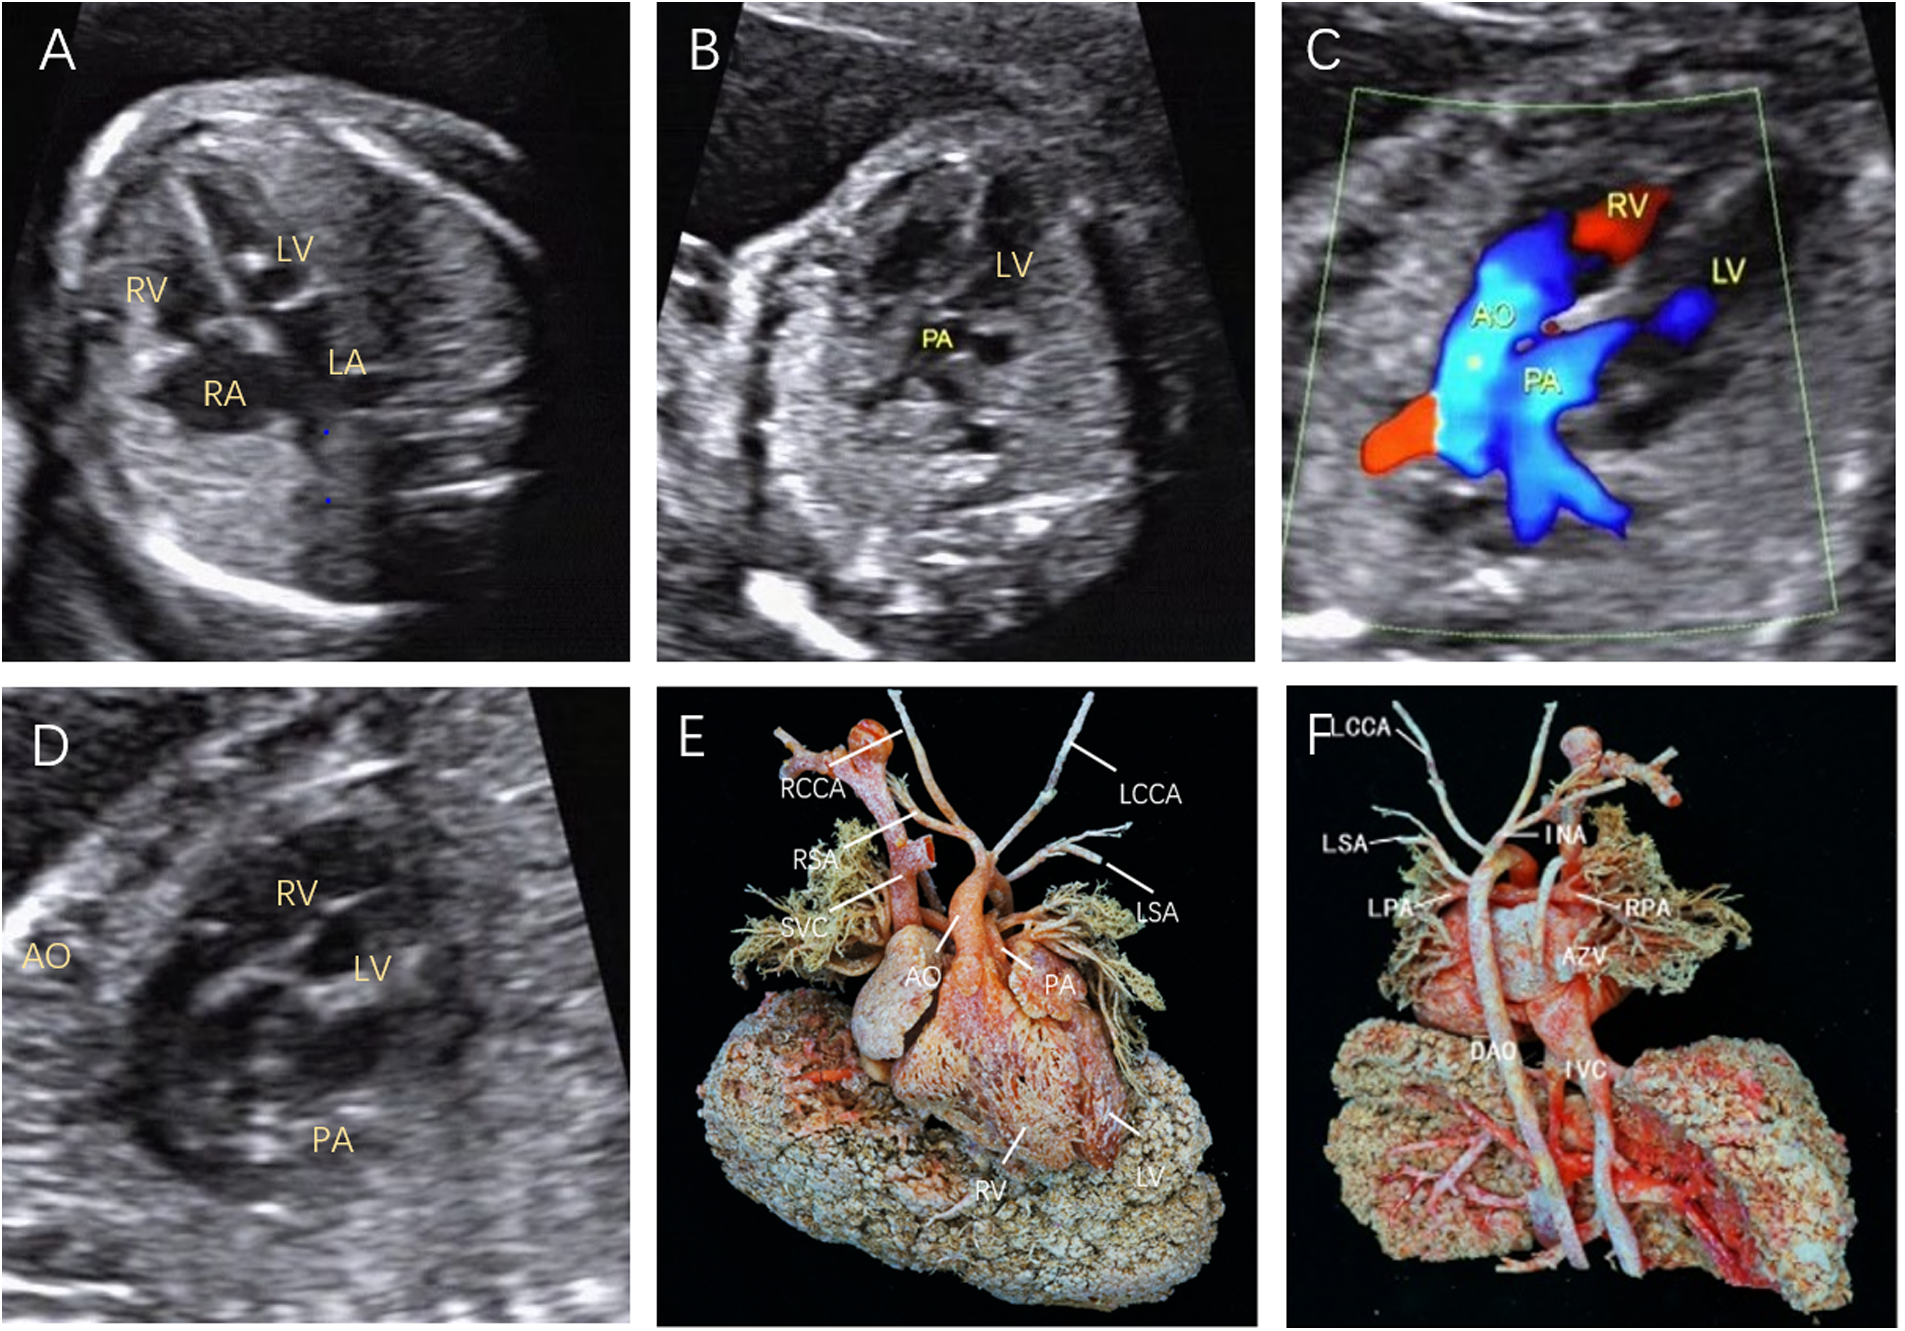

Figure 2

Fetal D-TGA was assessed via echocardiography at 23 weeks and 1 day. (A) Four-chamber view with consistent atrioventricular connections and strong dotted echogenicity of the left ventricle. (B) Five-chamber view showing the pulmonary artery emanating from the left ventricle and bifurcating into the left and right pulmonary arteries a short distance from the beginning of the artery. (C) Two large arteries aligned in parallel, with the aorta emanating from the right ventricle and located anteriorly to the pulmonary artery. (D) Long-axis view of the great vessels: the aortic arch emanates from the anterior right ventricle, followed by the head and neck vessels, which curl backwards in a ‘hockey puck’ shape, and the pulmonary artery follows a ‘crutch’ shape in the long-axis view. (E) Anatomical cast: frontal view. F: anatomical cast: dorsal view.